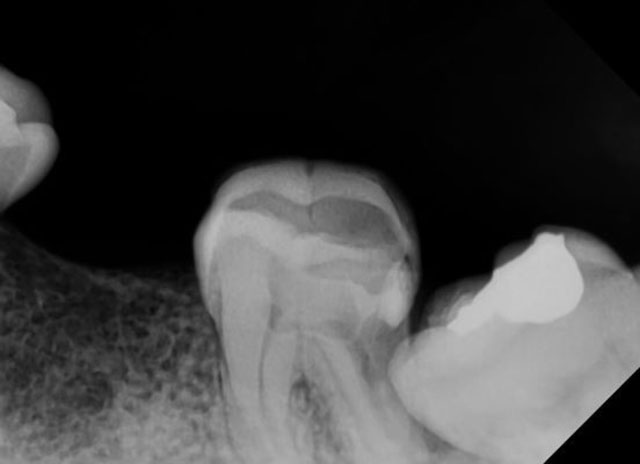

從X光片中看到你智慧齒傾斜,導致前面大牙蛀牙並擴展至牙髓神經。可以選擇的方法很多,要配合其他臨床檢查和其他X光才能給你一個完美答案。因為,沒有最好的方案,只有最適合你的方案。 我會建議你去找專業的牙科醫生拍攝3D CBCT,看清楚1. 智慧齒的牙根是否靠近神經線,2. 前面大牙的牙髓神經 和 3.前面缺失大牙的牙骨狀態。

舉個例子,倘若你想保留大牙,你便需要智慧齒手術來拔掉智慧齒 並且大牙進行根管治療(杜牙根)。